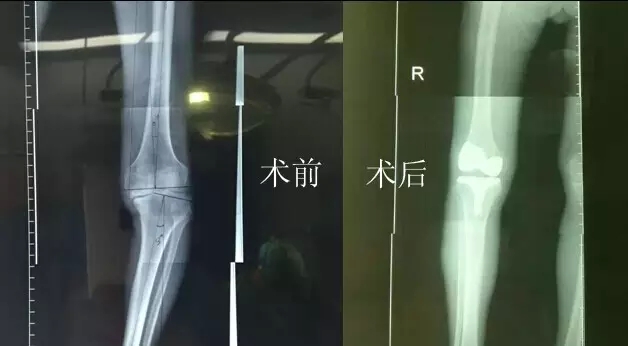

2月26日,嚴(yán)老伯在廣安醫(yī)院關(guān)節(jié)科做了膝關(guān)節(jié)表面置換手術(shù),從切開到縫合結(jié)束僅花了一個(gè)半小時(shí)。手術(shù)全過程病人基本上沒有手術(shù)后切口疼痛感,出血量不到150ml。術(shù)后第二天,他的右腿就能伸直了。

今天上午,主治醫(yī)生危立軍巡查病房時(shí)說:“嚴(yán)老伯的手術(shù)很成功,病人是非常嚴(yán)重的屈曲攣縮并內(nèi)翻畸形,膝關(guān)節(jié)平臺(tái)內(nèi)側(cè)骨缺損很嚴(yán)重。但我們采取了目前國(guó)際上最先進(jìn)的手術(shù)方法,無痛化病房管理和快速康復(fù)理念,所以病人恢復(fù)很快。”

據(jù)了解,以前像做這樣的手術(shù),病人大概需要休息兩個(gè)月左右才能逐漸康復(fù),而采取新的手術(shù)方法,按照嚴(yán)老伯目前恢復(fù)的情況,不需要什么特殊康復(fù),一周左右就能下地行走,兩周后就能出院。嚴(yán)老伯和家人對(duì)這次手術(shù)也表示非常滿意,他的關(guān)節(jié)內(nèi)翻也恢復(fù)到正常人一樣。